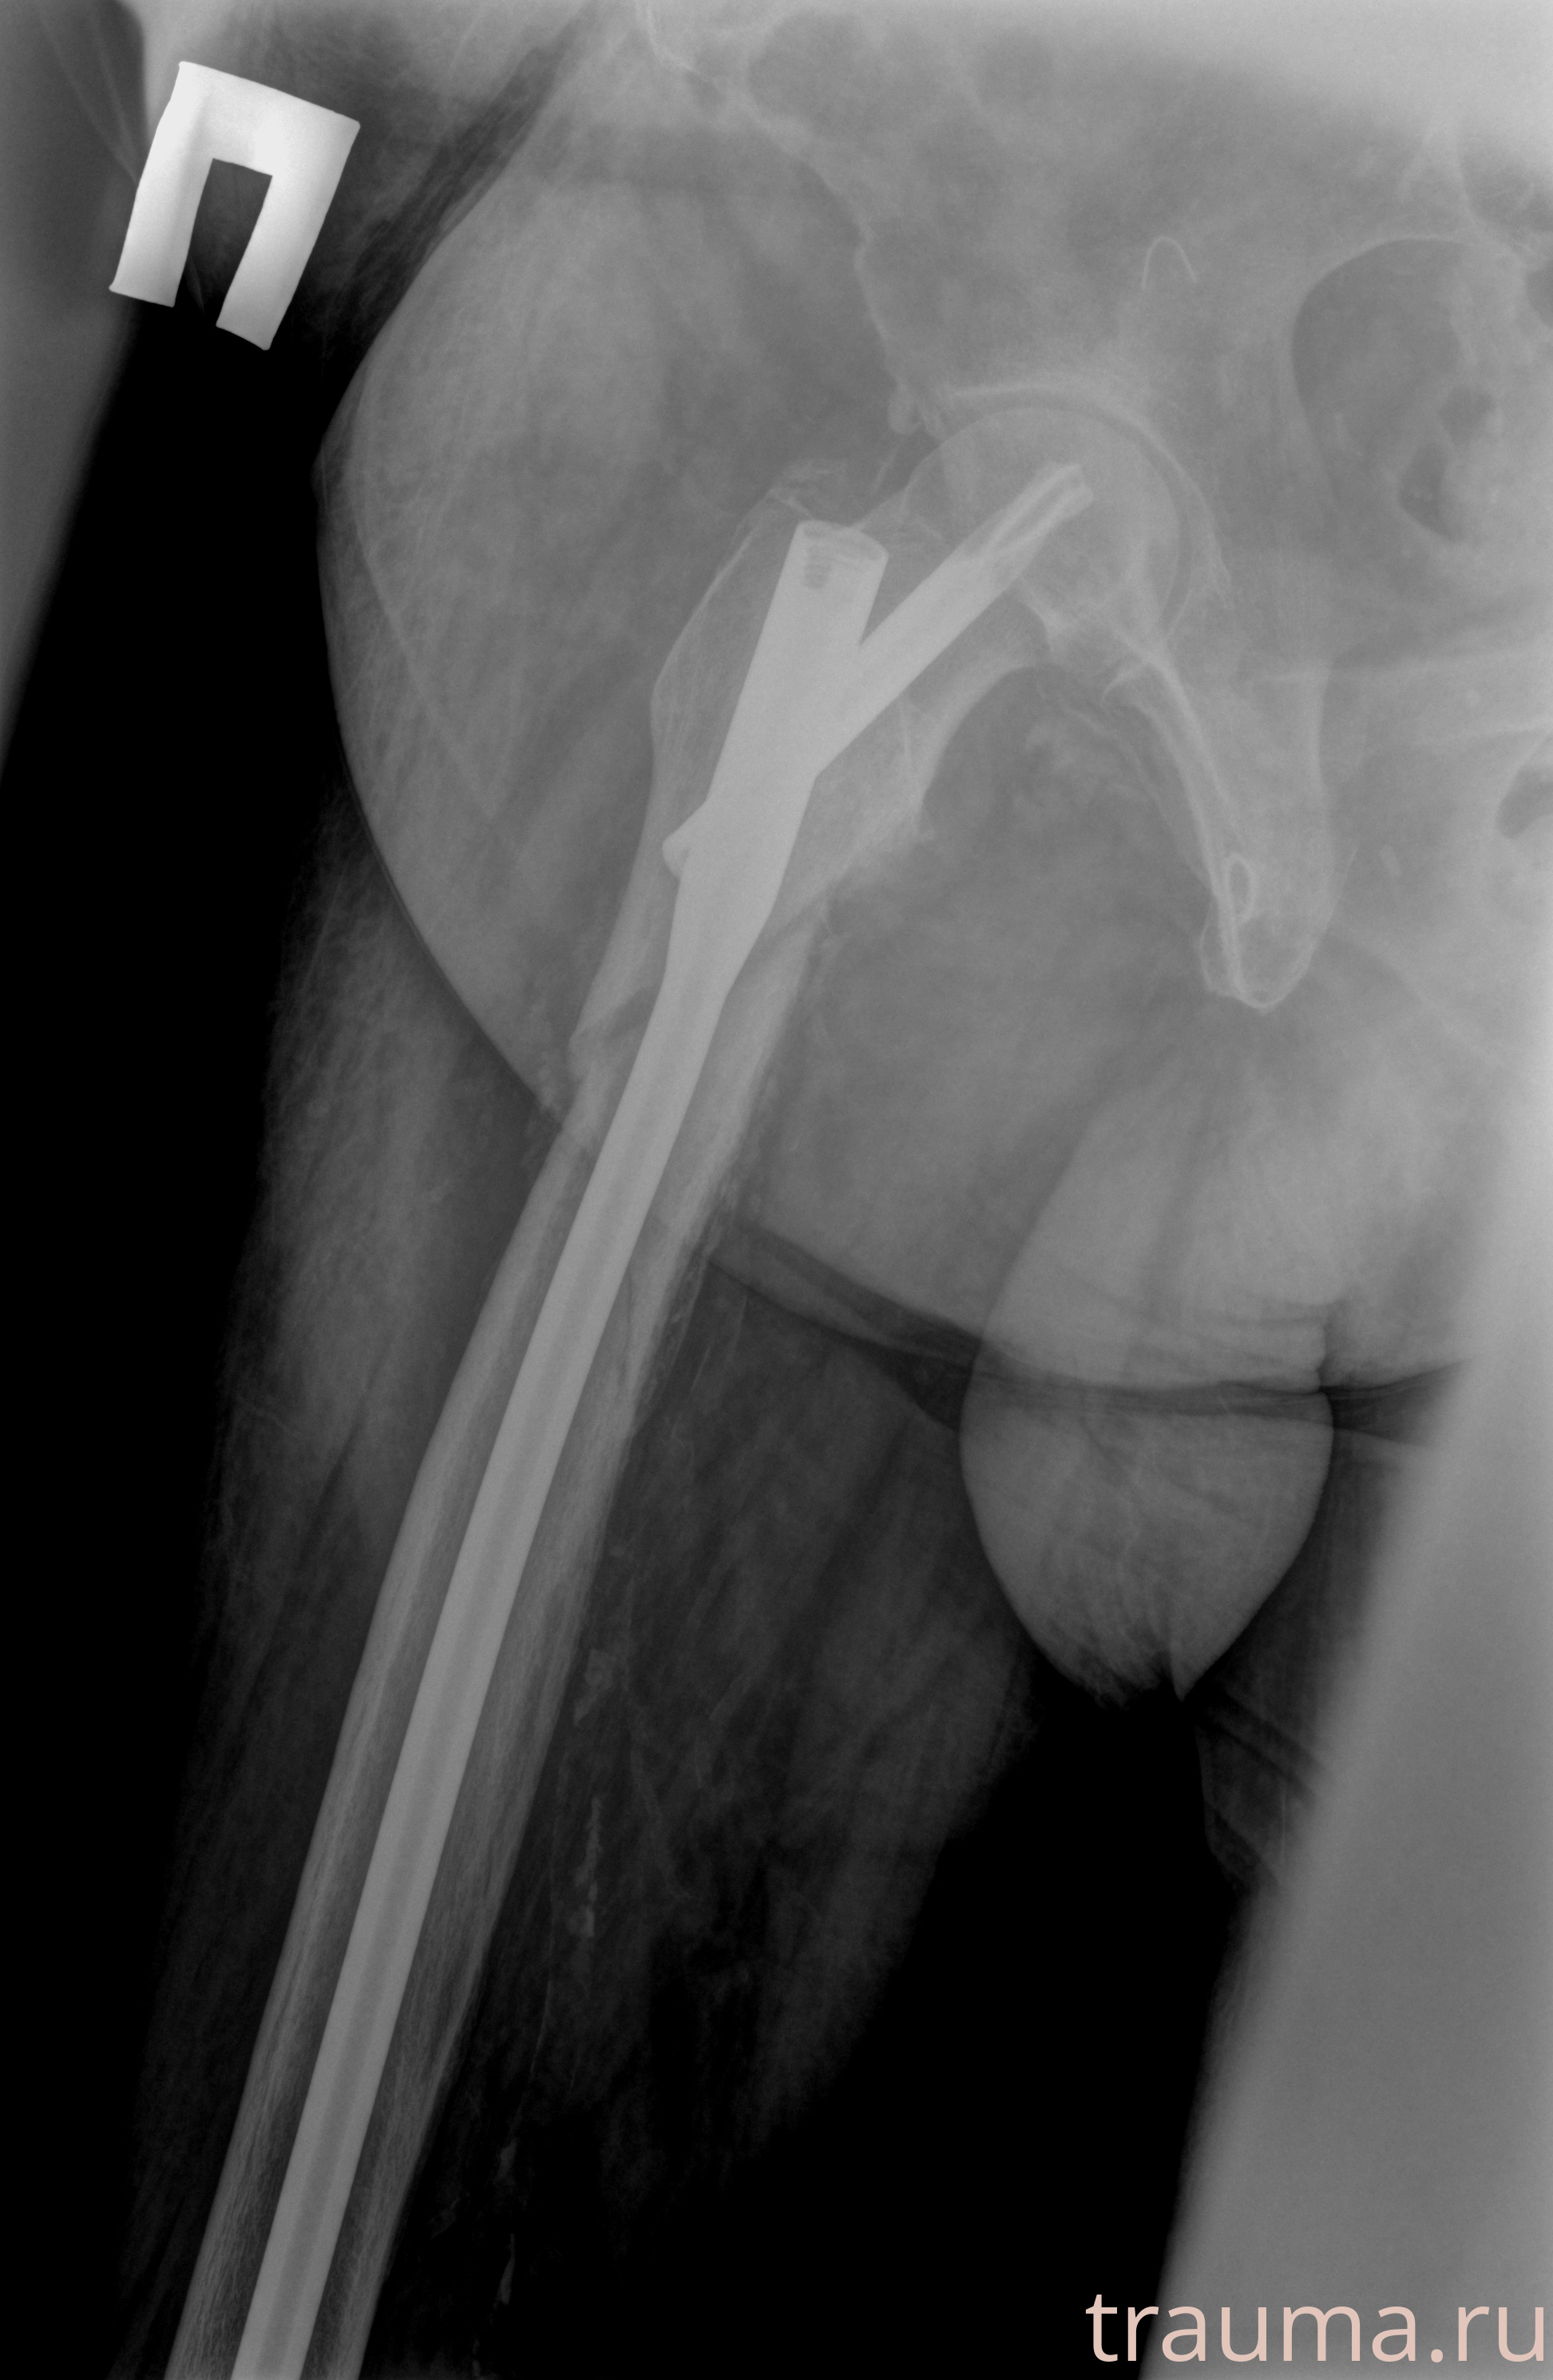

Рентгенограммы

Рентген на дому: по вашему адресу приезжает врач-рентгенолог, травматолог-ортопед с мобильным рентгеновским аппаратом, проводит диагностику травмы или заболевания, делает необходимые рентгенограммы, дает рекомендации по дальнейшему лечению. Получить качественные снимки в домашних условиях возможно благодаря уникальной методике, разработанной МосРентген Центром для института  Склифосовского